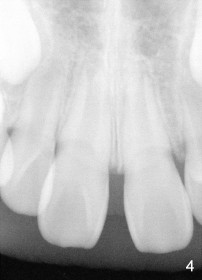

Eight-year-two-month girl has diastema between the maxillary central incisors.  It appears that the upper labial frenum (Fig.3 arrowheads, mirror view) bisects the interdental papilla (Fig.5).  Frenectomy is planned before orthodontic closure of the diastema.  Fig.4 is pre-op X-ray. Five months later, the diastema is closed.  The frenum appears to recede upward (Fig.6).  The bisected papilla seems to fuse (Fig.6,7).  Although the diastema has tendency to relapse when power chains are not used, fixed lingual retainer is planned to prevent the relapse when brackets are to be removed.  It appears that frenectomy is not so highly necessary for this purpose.